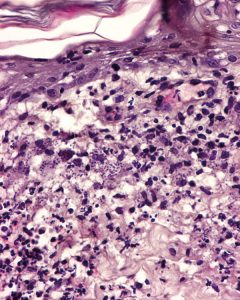

Four 8 mm skin punch biopsies were obtained. The histopathological study revealed a mononuclear dermatitis from nodular to diffuse with the presence of Leishmania amastigotes inside macrophages (Fig. 3).

- Fig. 5: Histological picture of the lesions in this case: mononuclear inflammatory infiltrate with a large number of leishmania amastigotes inside macrophages

Hass presented an unusual form of leishmaniosis with a papular cutaneous process in the absence of systemic signs of disease. Presence of leishmania amastigotes in skin biopsy diagnosed the infection, indicating the direct participation of the parasite in the inflammatory reaction causing the dermatological condition. The systemic involvement must always be assessed by complementary blood tests: haematology, blood biochemistry, leishmania serology and protein electrophoresis.